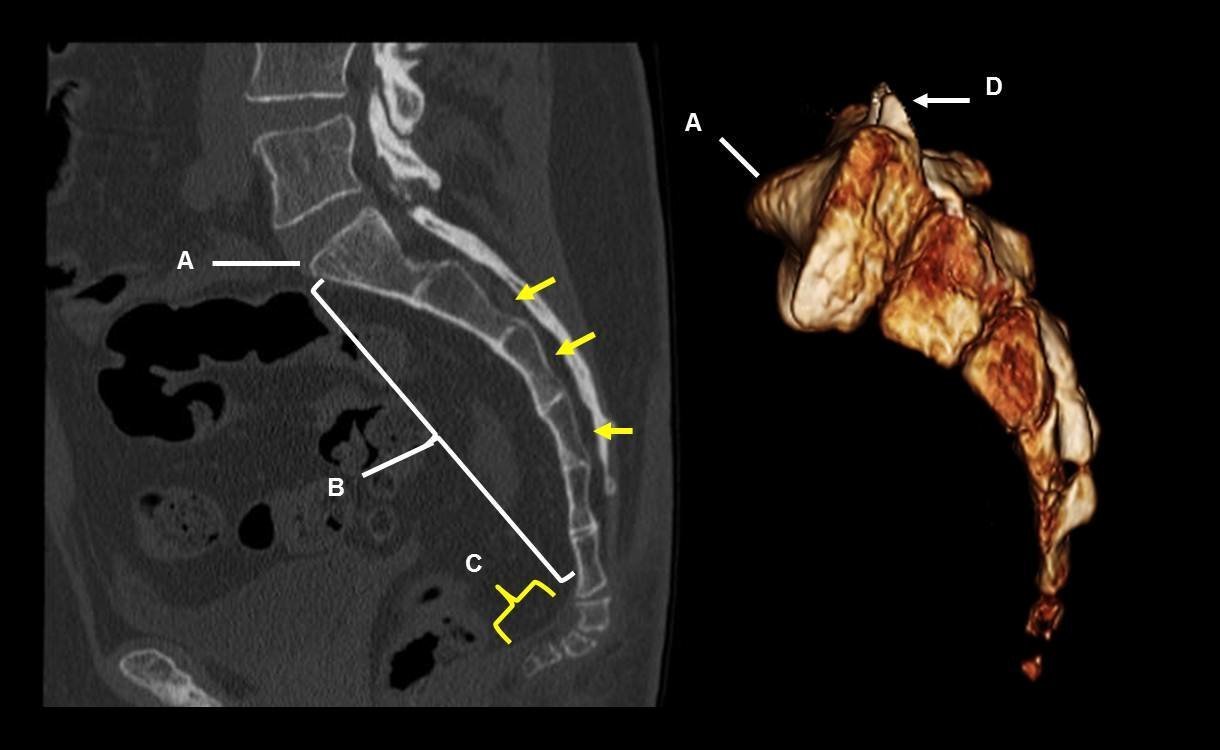

Перелом копчика. КТ в боковой проекции и трехмерные реконструкции.

Современные модели томографов позволяют построить объемную модель копчика, которую врач на экране монитора может рассмотреть со всех сторон, повернуть, увеличить, приблизить. Все это расширяет возможности врача в плане выявления заболеваний и повреждений крестца и копчика.

- переломы или смещение позвонков копчика, положение отломков позвонков;